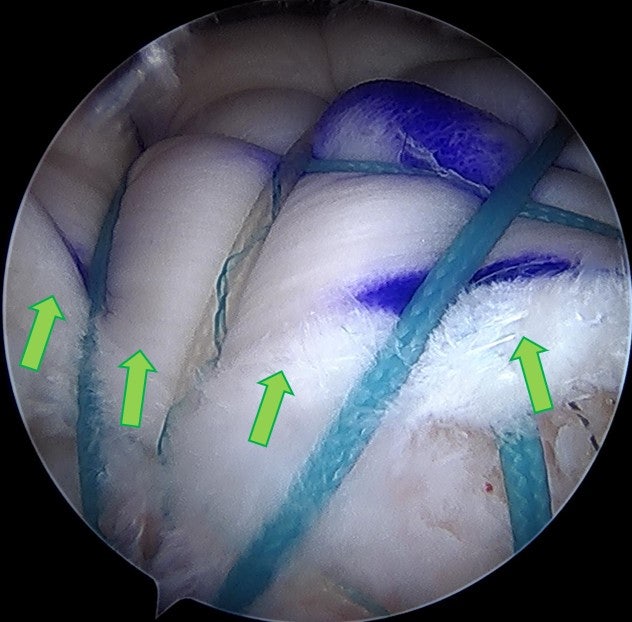

수술을 원래 계획했던 대로 allomend 를 이용하여 회전근개 봉합술 및 봉합술을 시행하였습니다. 수술 직후 MRI 영상으로 확인해 보았습니다.

광범위한 회전근개 파열이 있는 경우 완전히 해부학적으로 복원되지 않는 경우가 있습니다. 할 수 있는 만큼만 봉합을 한 경우 회전근개의 부착 부위가 원래의 해부학적으로 부착하는 것보다 적어지기 때문에 재파열이 발생할 가능성이 있고 회전근개의 기능의 회복도 잘 되지 않을 가능성이 많습니다. 이러한 경우 인조인대를 이용하여 보강술을 해주면 원래의 모양대로 해부학적인 복원이 가능하게 됩니다. 인조인대를 이용한 보강술을 술기가 복잡하고 어렵게 때문에 이러한 수술을 하는 병원이 많지는 않습니다. 모든 수술의 원칙은 손상된 조직의 해부학적인 복원입니다. 이를 할 수 없는 경우라도 최대한 근접하게 복원하는 것이 좋은 결과를 위해 매우 중요하다고 생각합니다. 환자분은 현재는 거의 정상적으로 활동하고 계시며 매우 만족하며 생활하신다고 합니다. 해부학적으로 복원 불가한 광범위 회전근개파열도 정상으로 회복될 수 있습니다!!!